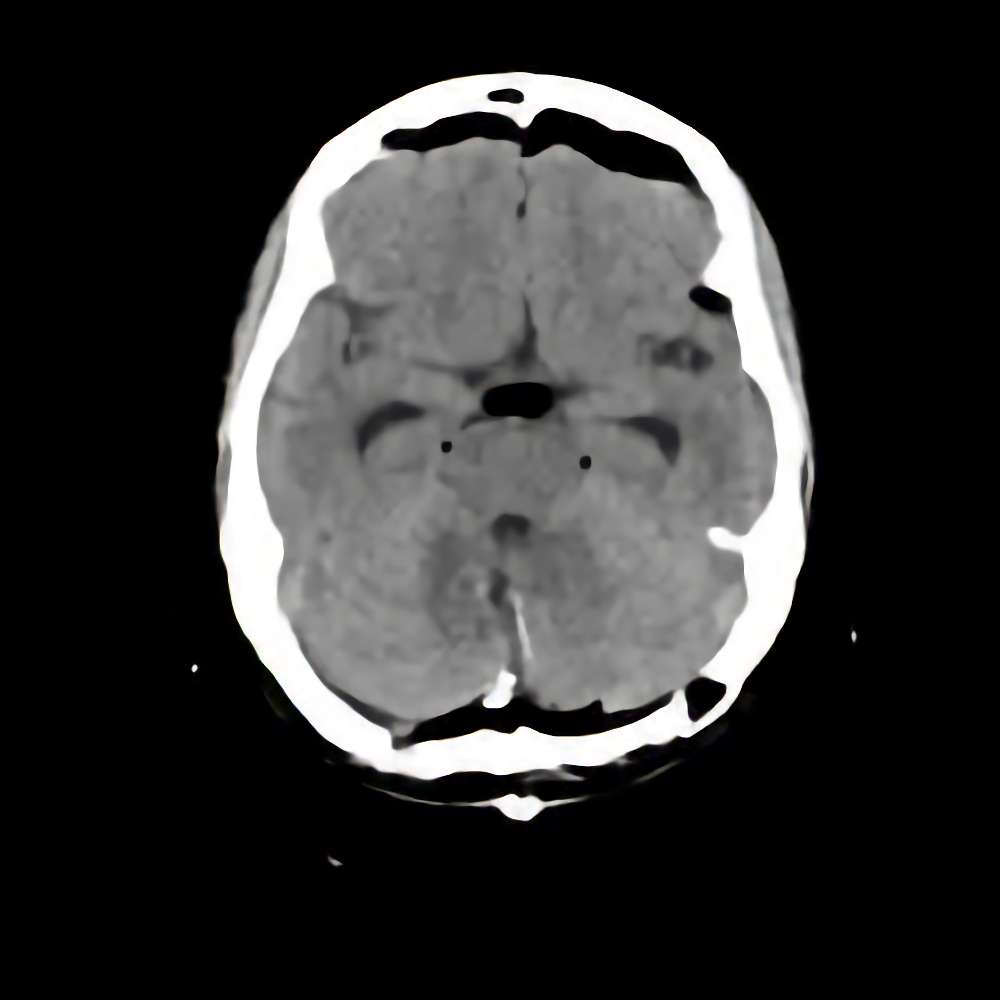

症例 '16年4月

No.

※ 画像をクリックすると拡大表示します。症例No.は平成29年から起算しています。

年_番号

手術年月

患者年齢

’16_60

'16年4月

40代

病名

術式

備考

静脈性血管腫

断層撮影

手術前

1

手術前2

手術後